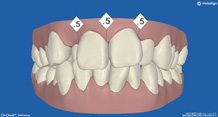

正面から観たところです。

全て乳歯です。反対咬合です。まだ幼児なので、お子様にかかる負担などをよく考えた上で、治療します。